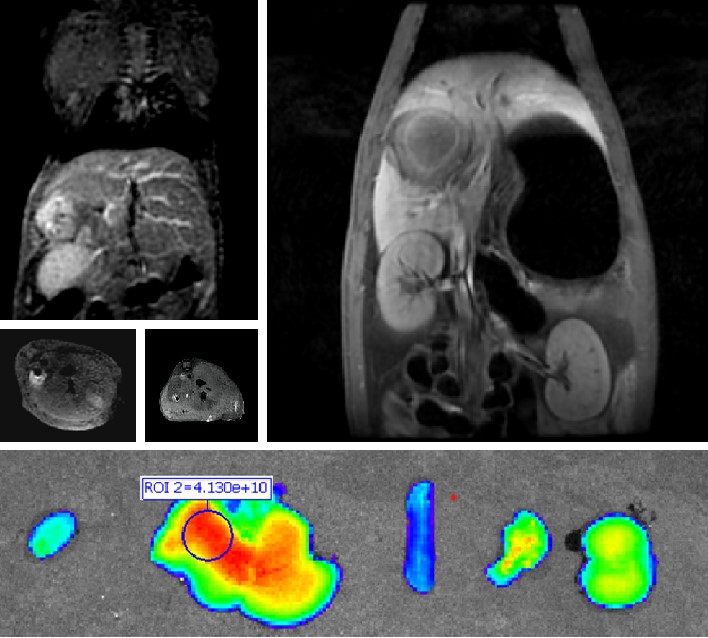

普利制药自主研发双模态造影剂PL002,首次提出通过整合磁共振技术,弥补现有荧光染料假阳性率高、透射深度有限等的短板,进而提升手术的精确性,降低手术过程中的风险,是全球首个获批临床试验的荧光/磁共振双模态造影剂,目前也已经获得美国FDA临床试验批件。